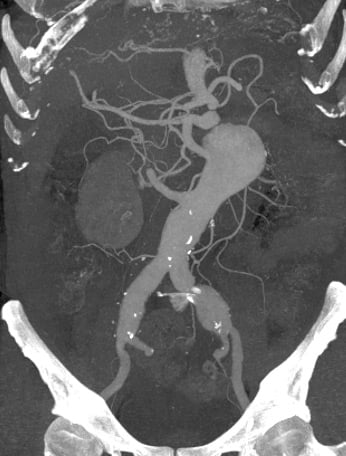

- Urgent CT scan: voluminous thoraco-abdominal aneurysm and bilateral iliac aneurysm

At CT scan control, 6 months after operation, the patient had a type-2 endoleak with enlargement of the aneurysmal sac.